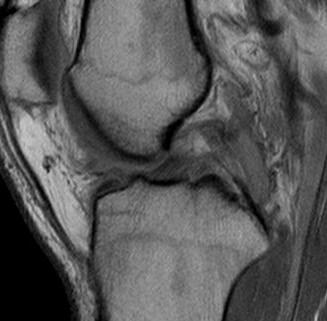

MRI

PCL midsubstance tear with lengthening

PCL tibial avulsion

PCL femoral avulsion